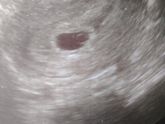

Ой, девочки, очень переживала… Почти не спала… Сегодня была на УЗИ, срок 5-6 неделе. Гинеколог сразу нашла мою крошечку. КТР 3,3. Сказала, что между 5 и 6 неделькой, но в заключении поставила 5 недель. Сердцебиение прослушивать, но его не измерять пока … Читать далее